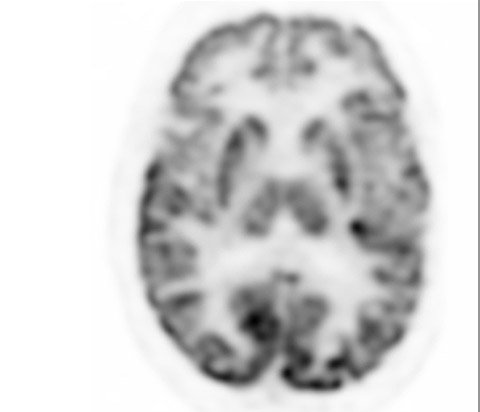

Mit der etwa zweimal höheren volumetrischen Auflösung gegenüber dem analogen System* zeigt der Vereos PET/CT-Scanner außergewöhnliche Details und hervorragende anatomische Bilder, wie die hier abgebildeten tiefen Strukturen des Gehirns. *GEMINI TF 16

Digitaler PET-Scan mit Vereos